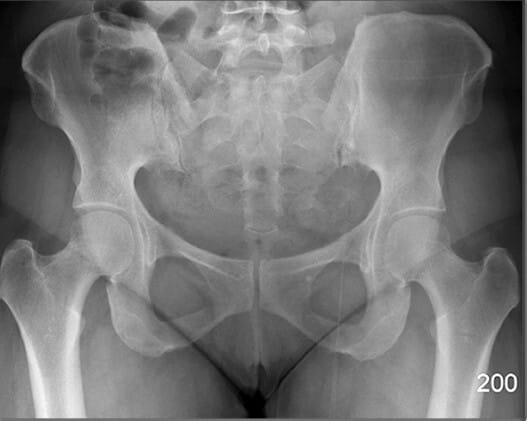

Pelvic Region

PELVIS

비구 (Acetabulum)

| 비구 (Acetabulum) |

| ✅ 대퇴골두(femoral head)가 삽입되는 골반 측면의 오목한 부분으로, AP view에서 둥근 원형 구조로 나타납니다. |

| 🔴골절, 탈구, 또는 관절 간격 이상이 있는지 확인하는 것이 중요합니다. |

폐쇄공 (Obturator Foramen)

| 폐쇄공 (Obturator Foramen) |

| ✅ 치골과 좌골 사이에 위치한 크고 타원형의 개구부로, AP view에서는 골반 하단 양측에 대칭적인 투과성 음영으로 보입니다. |

| 🔴 골반 골절에서 비대칭이나 모양 변화가 나타날 수 있는 부위입니다. |

천장관절 (Sacroiliac Joint)

| 천장관절 (Sacroiliac Joint) |

| ✅ 천골과 장골 사이의 관절로, AP view상에서 좌우 대칭적으로 좁고 긴 틈으로 관찰됩니다. |

| 🔴 간격이 좁아지거나 불규칙한 경우 염증성 질환(예: 강직성 척추염)을 의심할 수 있습니다. |

FEMUR

대퇴골두 (Head of Femur)

| 대퇴골두 (Head of Femur) |

| ✅ 비구에 삽입되어 고관절을 이루는 구형 구조물로, AP view에서 관절 중심부의 둥근 음영으로 나타납니다. |

| 🔴 대퇴골두의 위치와 관절 간격을 통해 탈구, 골괴사 등을 평가할 수 있습니다. |